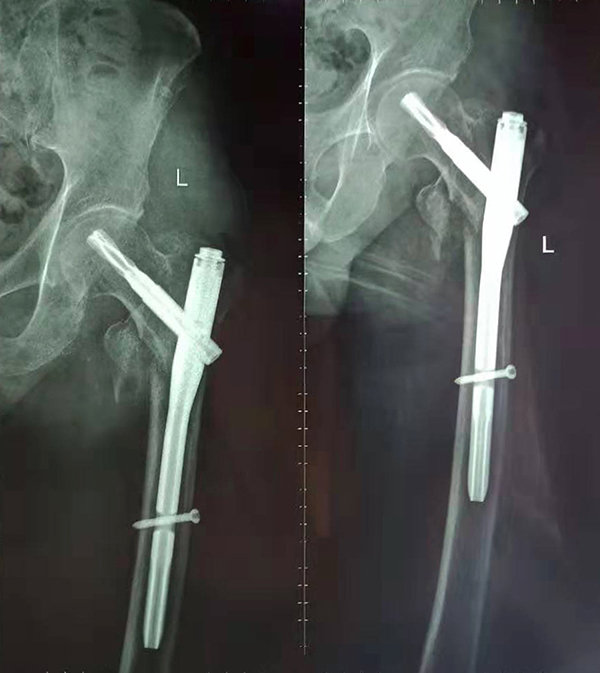

經(jīng)術(shù)前仔細(xì)的檢查和評估,與張爺爺家屬充分溝通,決定了實施閉合復(fù)位PFNA內(nèi)固定術(shù)的方案,劉鴻程主任說到,該術(shù)式的創(chuàng)傷小、出血少,適合骨質(zhì)疏松病人,術(shù)后解除患者疼痛,可以早期開始活動,便于護(hù)理。

手術(shù)后

9月10日上午,骨科順利完成張爺爺?shù)淖蠊晒谴致¢g骨折髓內(nèi)釘內(nèi)固定術(shù)。手術(shù)過程中麻醉平穩(wěn),術(shù)中出血量少,骨折手術(shù)時間持續(xù)一個多小時。